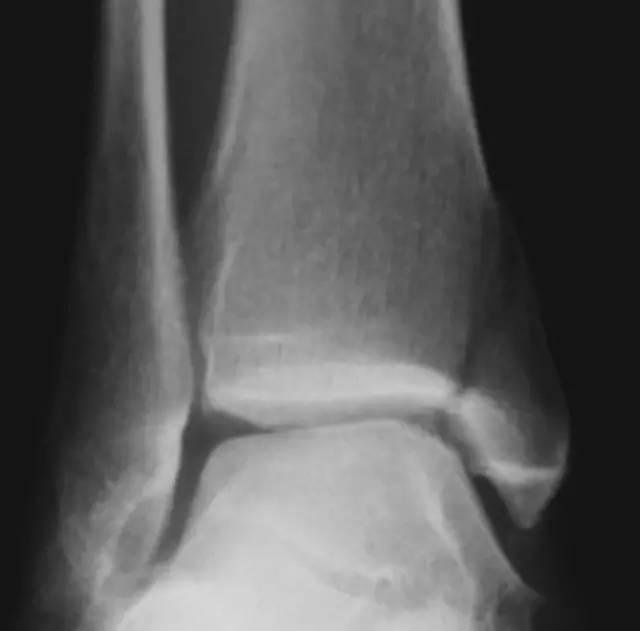

典型的垂直型骨折

内踝内收型损伤,关节面存在塌陷,这是一种严重的损伤,术中需要复位塌陷的关节面。